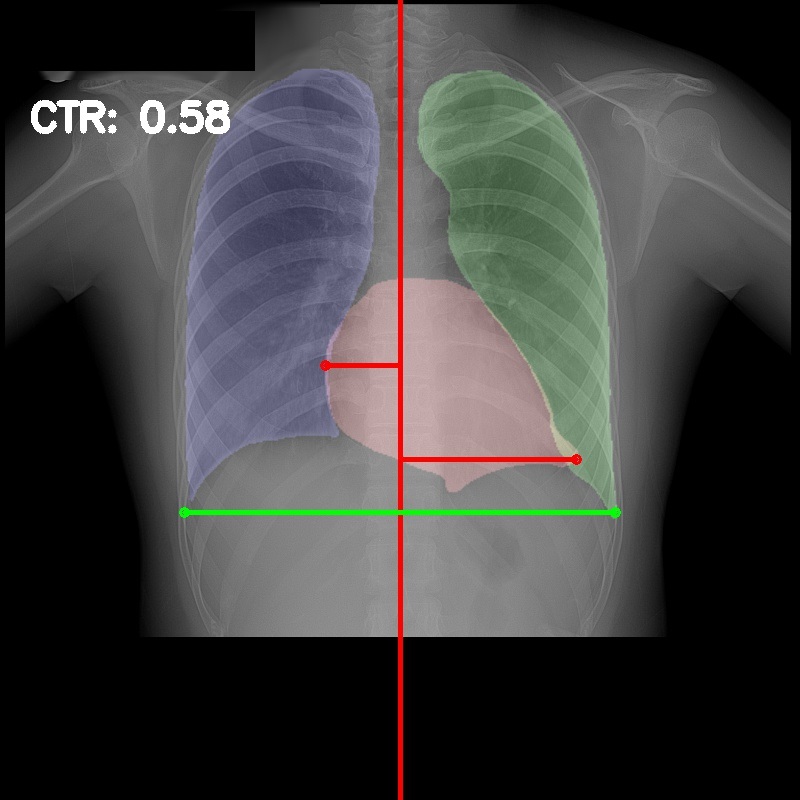

3.5 Cardiothoracic Ratio Calculation

After obtaining the masks, we calculate CTR with equation 1. We calculate cardiac diameter, , by finding the extreme points on the x-axis of the heart mask and calculate their x-axis distance. Thoracic diameter, , is calculated from extreme points from the lung mask. Figure 4 demonstrates the calculation of each component.

After obtaining heart and lung segments, we calculated , , and and marked them on the image along with CTR value calculated from Equation 1.

Figure 6 shows examples of our CTR calculation, where CTR values along with their , and measurement points are correctly identified. In this image, cardiomegaly is correctly detected by CTR value of .

Figure 7 shows cases where our CTR calculation algorithm is incorrect due to failure to obtain accurate heart mask.

However, upon manual inspection of the images, we found a relatively high number of mild cardiomegaly cases that are not included in the dataset labels. Figure 8 shows sample chest X-ray images containing no-cardiomegaly labels with detected CTR values on range. This reflects the general sentiment that dataset labels are noisy and may contain errors, making it harder to analyze our algorithm. It also illustrates the value of an algorithmic "second opinion" to catch potential errors from both human and NLP algorithms used to generate the labels.